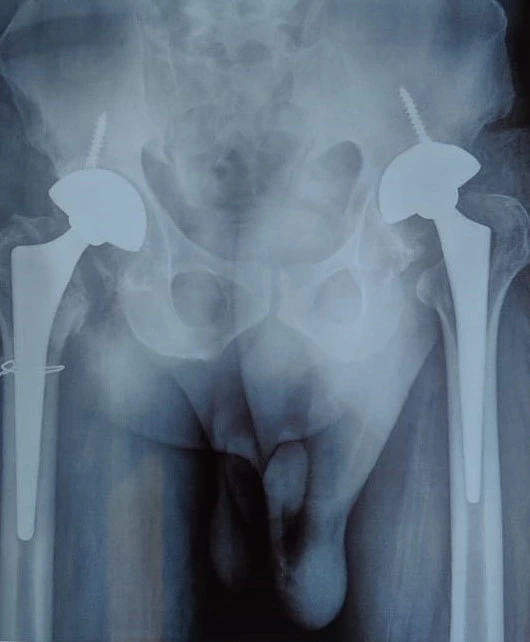

Quality and affordable healthcare has long been the essence in the field of medical sciences & treatment. Every patient expects an early diagnosis and a planned approach to treatment procedures with affordability and access to quality healthcare. Knee replacement, Hip replacement, Fracture treatment are being done by Dr.P.Sankaralingam at very affordable costs without compromising on quality.

Dr.P.Sankaralingam M.S(ortho)., DNB (ortho).,MNAMS is an experienced senior consultant Orthopaedic surgeon who does about 350 joint replacement surgeries per year in addition to treatment of Trauma cases.

Standard Hospital, Chennai’s Centre of Excellence for Orthopaedics offers minimally invasive surgeries for faster recovery.